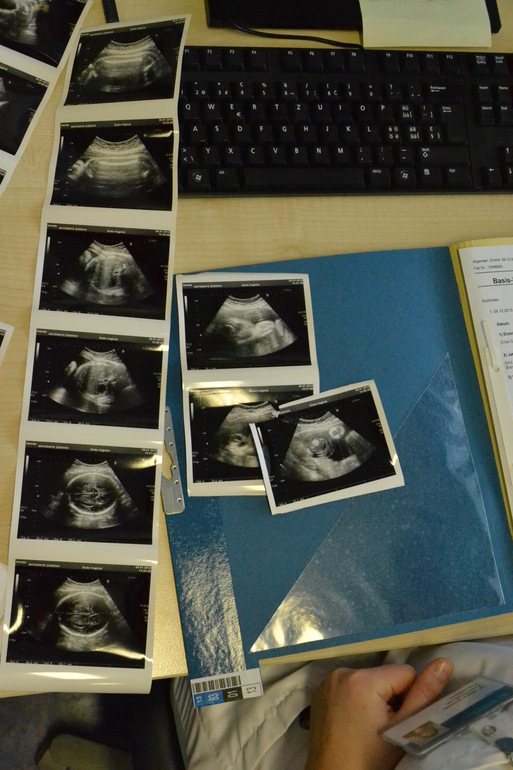

Наши недавние фото УЗИ

Пузяши наши, ВДМ, тазНаши УЗИ на 31н+6дн и фото пузика от 16+4 до 32+5

Лицо хорошо видно,черты лица кстати сильно отличаются от предыдущего УЗИ почему-то,на прошлом носик был такой маленький,а на этом очень большой,а у вас лицо после рождения отличалось от того что на УЗИ видно?

нам на каждом узи по многу фоток делают,но правда половину они себе забирают,но я тоже клянчу типа "ой,а можно еще и эту и вот эту"))))ну это правда зависит где делают,на 20-ой неделе мы в другом месте делали,так нам вообще ни одной не сделали даже...